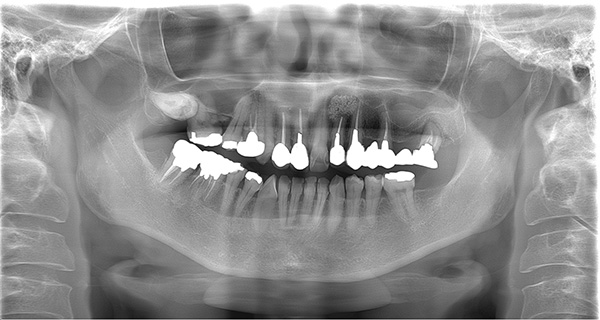

| 年代・性別 | 50代 男性 |

|---|---|

| 主訴 | 右上下の歯が痛い |

| 治療期間 | 約12ヶ月 |

| 費用 | 2,500,000円 |

| 治療内容 | インプラント、骨造成、結合組織移植、セラミック修復 |

| 治療に伴うリスク | インプラント周囲炎 セラミックの破折、脱離 |

*キャンセルポリシーをご一読のうえご予約ください